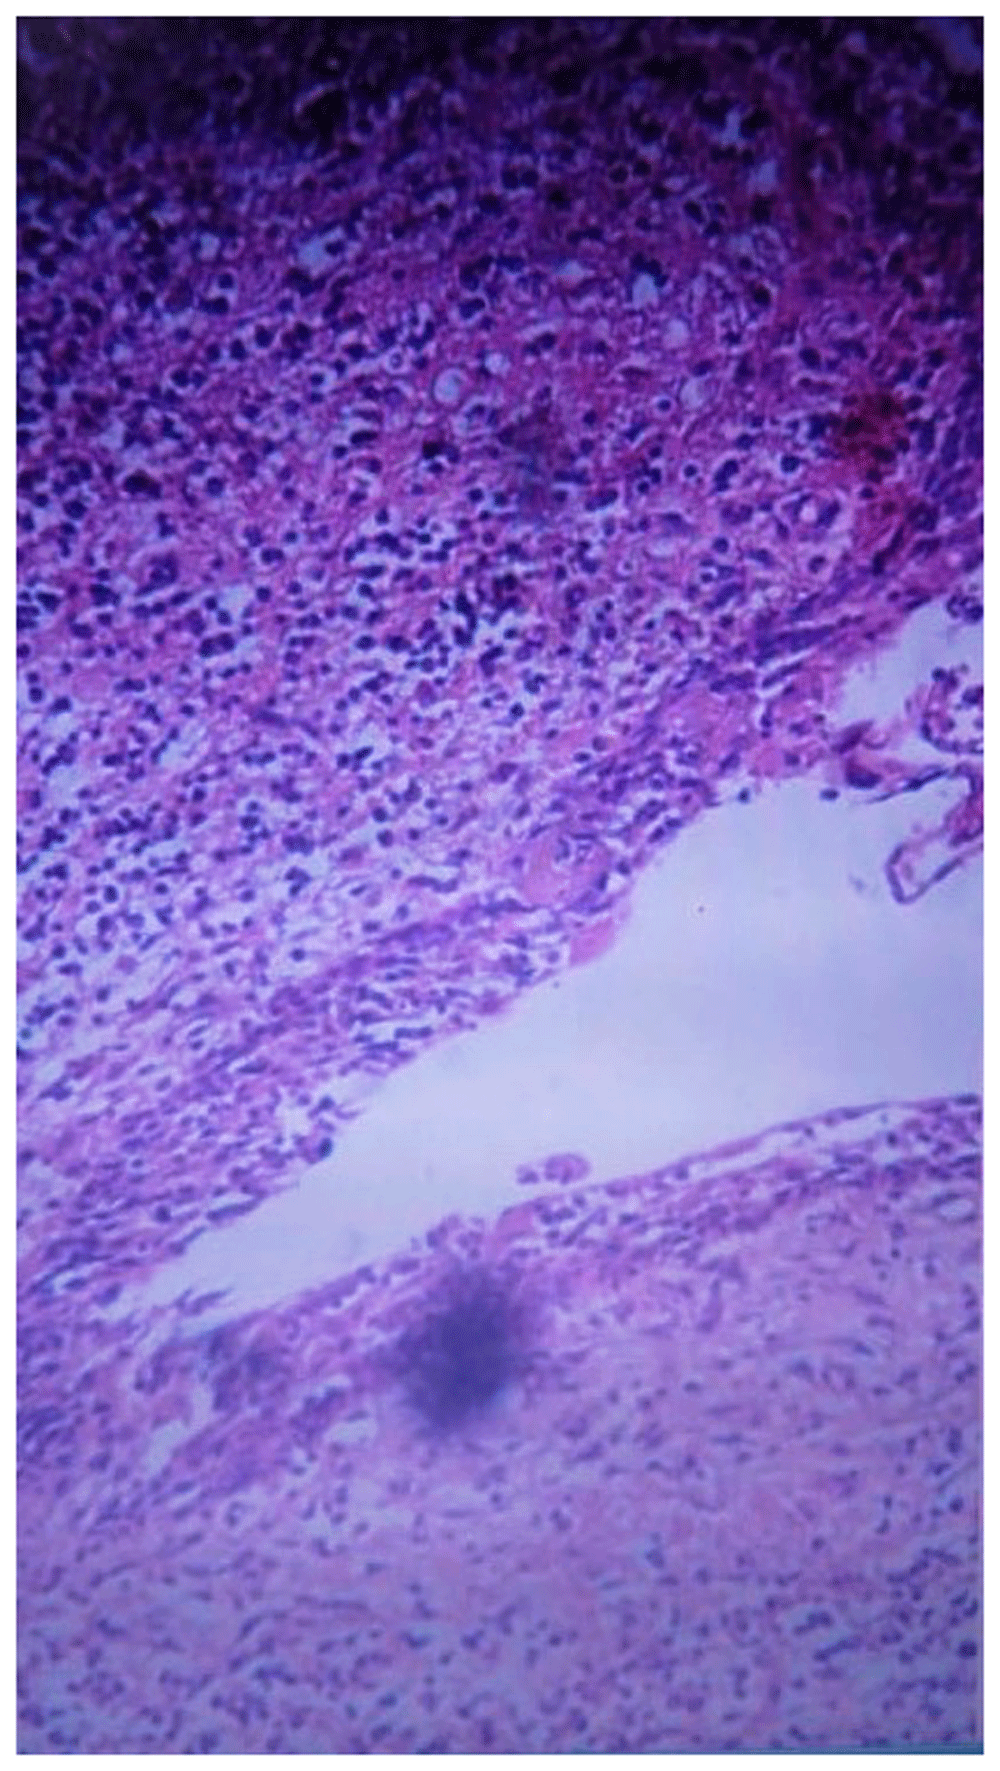

The specimens were sent to the histopathology laboratory in two containers. The histopathologic analysis of the multiple serial sections of the two specimens revealed multiple pieces of cyst wall lined by small strip of non-keratinized stratified squamous epithelium with mixed inflammatory reaction and surrounding edematous granulation tissue formed of numerous proliferating capillary type vascular spaces. Also, the specimens under the microscope showed bland looking spindle-shaped fibroblasts and degenerated bony spicules, which was consistent with cystic lesions (Figure 3). Based on the clinical examination, radiographic interpretation, and histopathologic analysis, the final diagnosis was bilateral BBC.